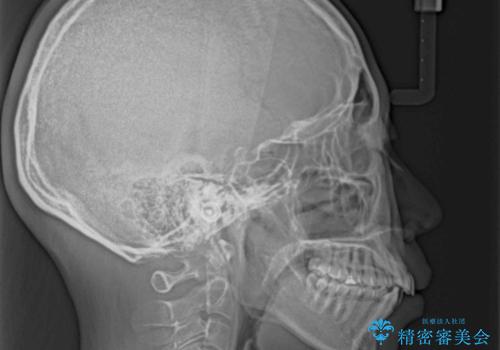

- 口元の閉じにくさを気にして来院された患者様です。

上下ともに歯列が前方に突出していたため、上下左右の第一小臼歯4本を抜去し、ワイヤー装置による矯正治療を行うこととしました。

舌の突出癖による影響もあったため、舌のトレーニングを並行して実施しました。

舌の突出癖がなかなか改善されず、上下前歯の接触がやや甘い状態での仕上がりとなりました。

接触が甘い場合、上顎前歯の叢生が後戻りを起こしやすくなるため、治療終了後の保定期間でも舌のトレーニングを継続するように指示しています。